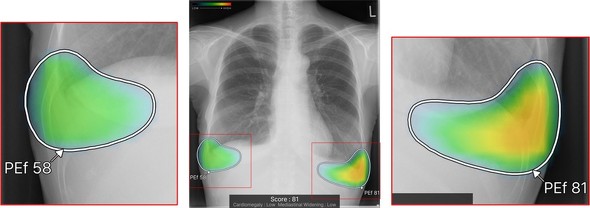

表示機能についても改良を加え、異常所見の存在可能性を色付けして示す「ヒートマップ表示」に加え、新たに「輪郭表示」と、これらを組み合わせた併用表示を選択可能にした。モノクロモニターを使用する読影環境においても視認性を確保できる。

キャプション 異常所見の存在可能性表示[クリックで拡大] 出所:富士フイルム

また、検出領域ごとに所見名と確信度を示すスコアを個別に表示する機能や、複数の所見が重なる領域でそれぞれの輪郭線を独立して表示する機能を実装し、詳細な画像診断をサポートする。

キャプション 所見名とスコアの表示[クリックで拡大] 出所:富士フイルム